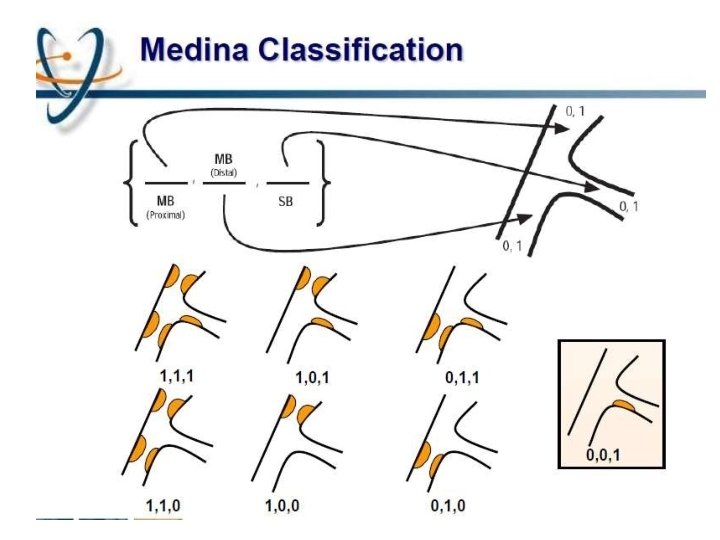

MEDINA classification

Limitations Does not take intoaccount 1. 2. 3. 4. 5. 6. Length of disease in the ostium of the SB Length of the LMCA before the bifurcation Trifurcation Vessel angulation No differentiation is madebetween a normal segment (lesion free segment) and a < 5 0 % lesion presenceof calcifications is not identified